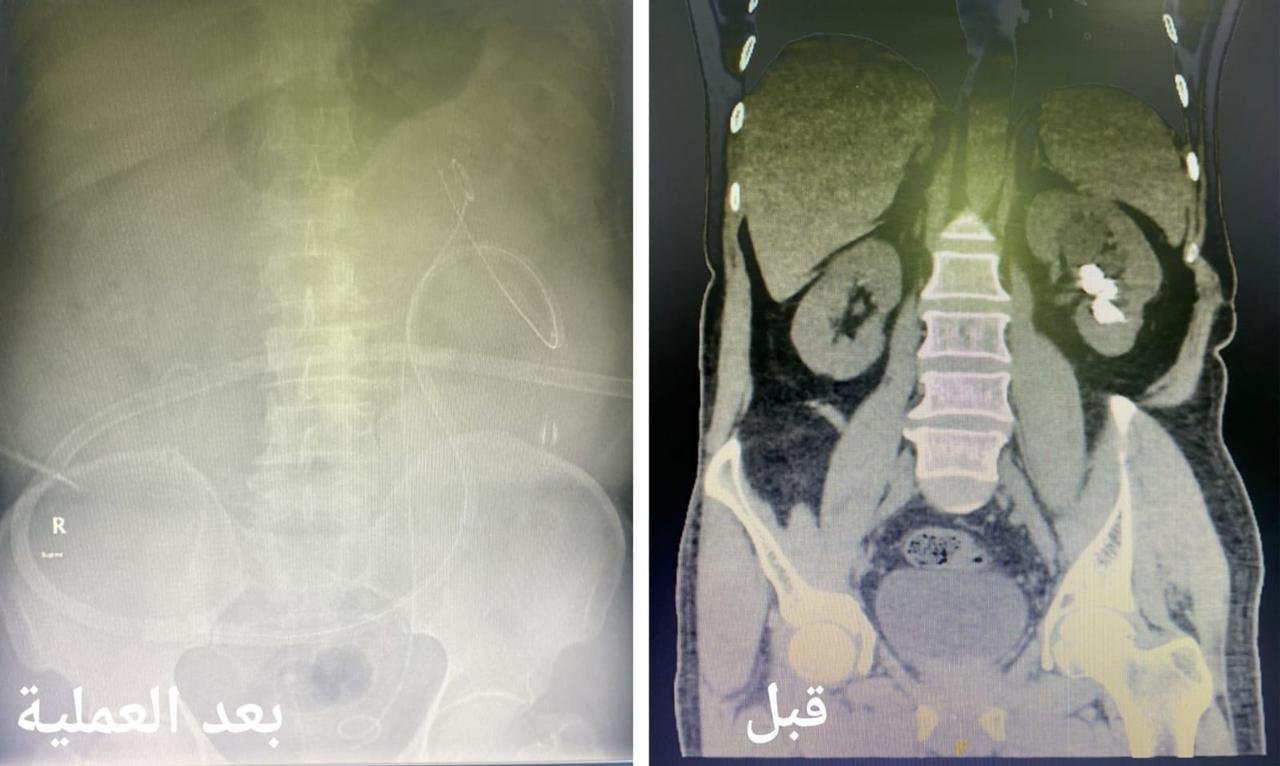

وقالت صحة جدة أن فريق طبي بقسم أمراض المسالك البولية في مجمع الملك عبدالله الطبي بجدة قرر إجراء التدخل الجراحي الدقيق بعد إجراء الفحصوات الطبية اللازمة للمريض الذي كان يعاني من آلام مزمنة في الجنب الأيسر من الجسم بسبب وجود حصوات في الجهاز البولي باستخدام التقنيات الطبية الحديثة .

وأكدت أن الآم إزدادت خلال الأشهر الأخيرة مع المريض مع وجود تاريخ مرضي قديم يؤكد وجود حصوات في الجهاز البولي تسببت له تلك الاعراض مما استدعى سرعة إستكمال الفحوصات الطبية اللازمة والفحوص المخبرية للدم و البول و الفحوص الإشعاعية التصويرية بالأشعة المقطعية تبين خلالها وجود حصوات في حوض و تجويف الكلية اليسرى بحجم 3 سنتيمتر .

وأضحت أنه تم تجهيز المريض ونقله لغرفة العمليات وعمل تدخل جراحي كلوي دقيق بشق سنتيمتر واحد في الجلد بإستخدام التقنيات الطبية الحديثة لإستئصال الحصوات في جلسة جراحية واحدة و إزالتها بالكامل بواسطة ( المنظار الجلدي الكلوي ) و جهاز التيليسكوب و أدوات طبية صغيرة الحجم حيث تم إغلاق الشق الجراحي بخياطة واحدة دون حدوث أي مضاعفات ولله الحمد